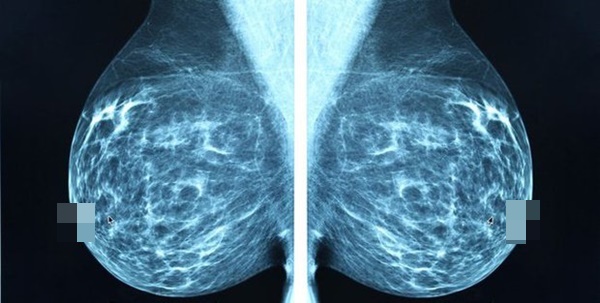

6. Mô vú dày đặc

Vú được tạo thành từ mô mỡ, mô sợi và mô tuyến. Bạn được coi là có "bộ ngực dày" nếu chụp quang tuyến vú cho thấy bạn có nhiều mô tuyến và mô xơ, ít mô mỡ hơn. Theo Hiệp hội Ung thư Hoa Kỳ, phụ nữ có bộ ngực dày (mô vú dày) có nguy cơ mắc bệnh ung thư vú cao gấp 1,5 đến 2 lần so với phụ nữ có mật độ vú trung bình.